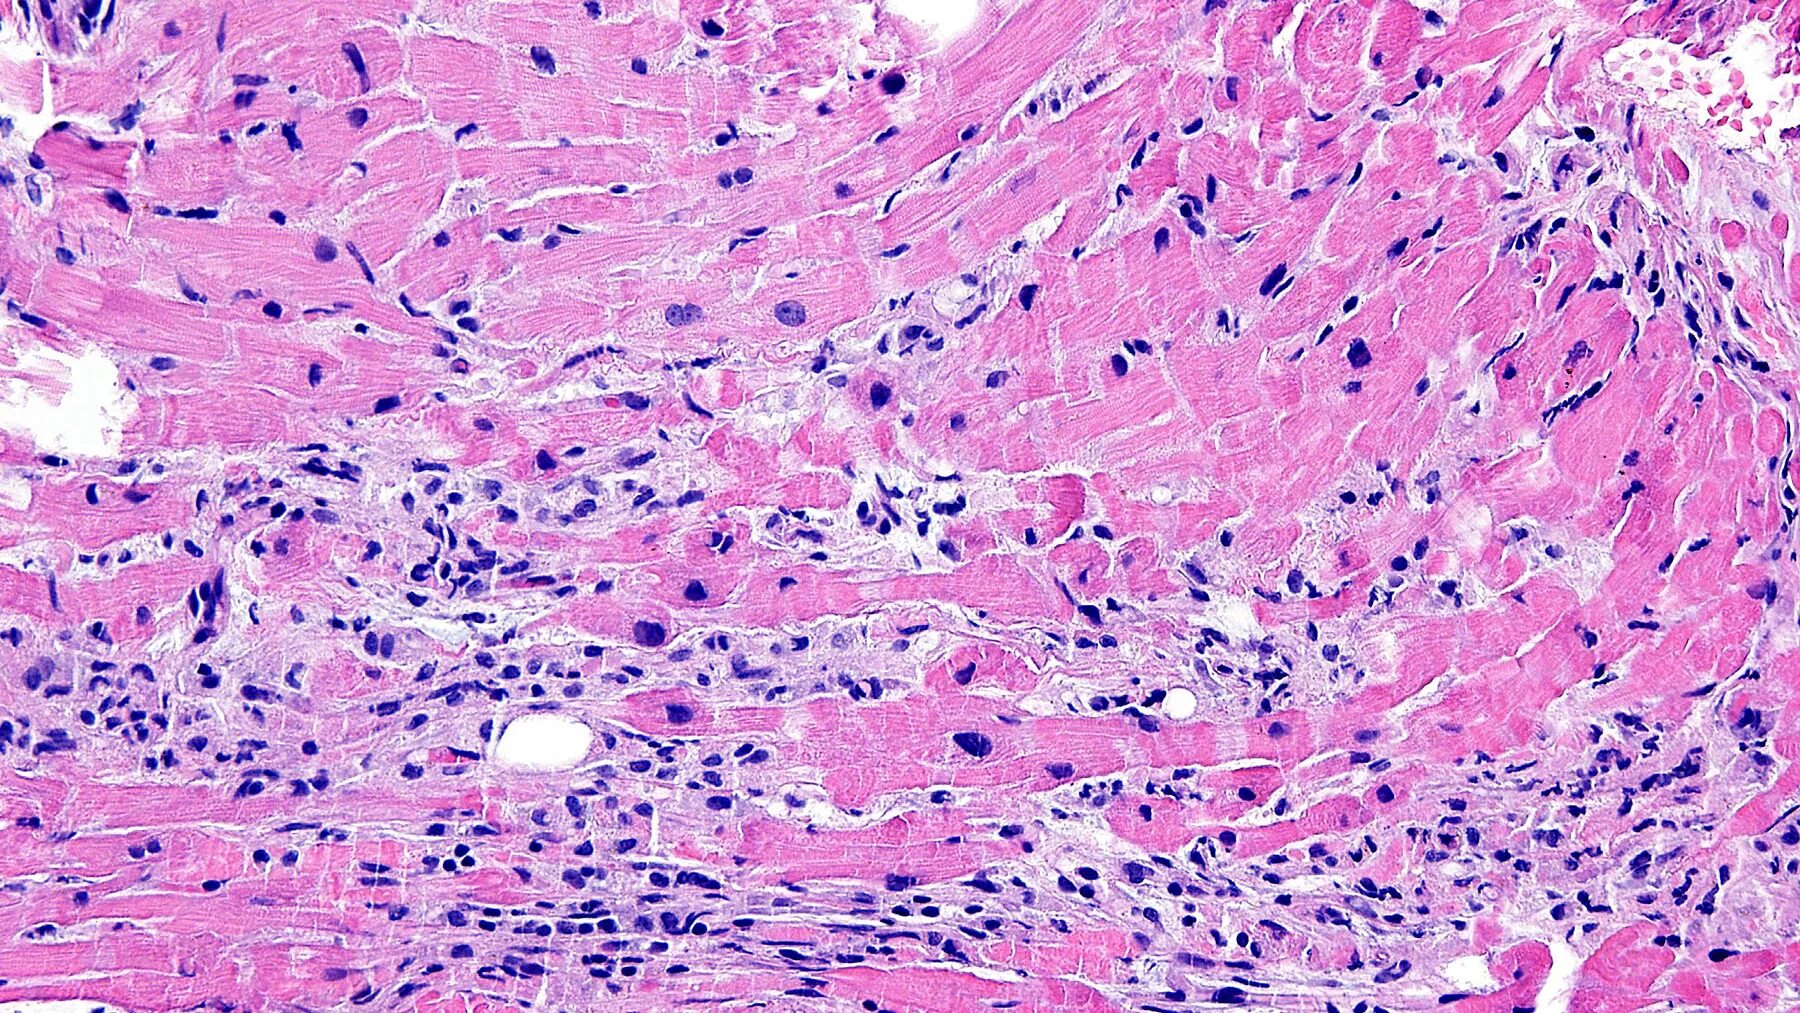

Диффузная лимфоцитарная инфильтрация